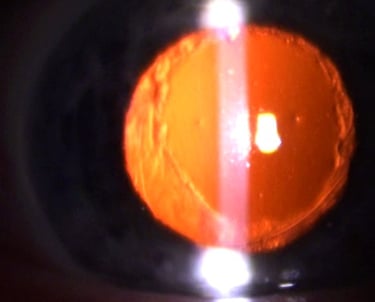

YAG Laser-Behandlung des Nachstars

Mit dem YAG-Laser kann ambulant in der Praxis nach Aufsetzen eines speziellen Kontaktglases in örtlicher Betäubung (Tropfanästhesie) der Nachstar durch zirkuläre, zentrische Eröffnung der hinteren Linsenkapsel dauerhaft entfernt werden, so dass die optische Achse wieder frei wird und das Sehvermögen in der Regel deutlich ansteigt. Der Eingriff kann in Tropfanästhesie ambulant in der Praxis erfolgen, eine Kontrolle am anderen Tag schließt die Behandlung ab. Benefit, Wiederherstellung bzw. Verbesserung des Sehvermögens bei Nachstar Laserbehandlung.